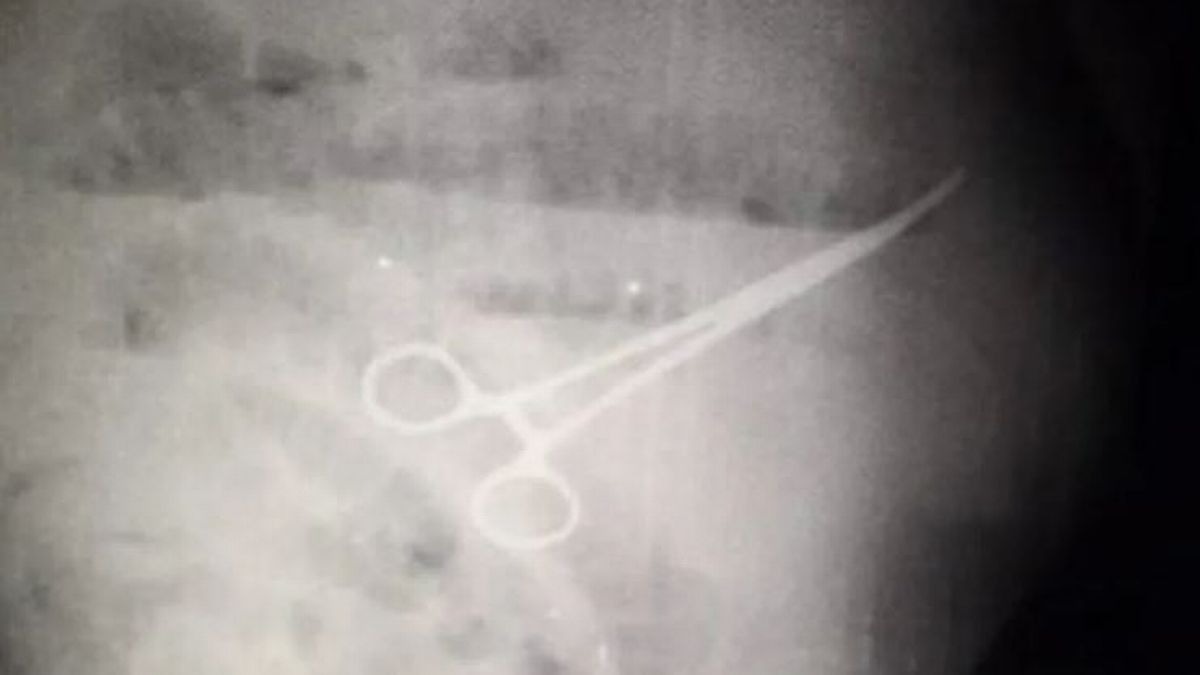

12/04/2022 18:09Bệnh nhân tử vong do bác sĩ để quên kéo trong bụng

Ông Ivan Chavez, 59 tuổi đã đến Bệnh viện Đại học Maracaibo, ở thành phố lớn thứ hai của Venezuela, để khám dạ dày. Sau đó ông được các bác sĩ kết luận phải tiến hành phẫu thuật để cắt túi thừa bị viêm, ca mổ được cho là đã diễn ra thuận lợi.

Tuy nhiên vài hôm sau, ông Chavez bắt đầu cảm thấy đau bụng, khó ăn uống và đi vệ sinh. Mặc dù các bác sĩ đã kê cho ông nhiều phương pháp điều trị khác nhau tuy nhiên, cảm giác khó chịu không giảm bớt.

Bốn ngày sau các nhân viên y tế quyết định tiến hành chụp X-quang và phát hiện có một chiếc kéo đã bị bỏ quên trong dạ dày của bệnh nhân. Ông Chavez lại thêm một lần nữa phải tiến hành phẫu thuật khẩn cấp tuy nhiên ông đã tử vong sau đó 5 ngày, gia đình nạn nhân đã đổ lỗi cho các bác sĩ vì làm việc cẩu thả.

Tuần trước, bác sĩ Freddy Pachano Arenas, người làm việc tại bệnh viện, đã thông báo trên Twitter rằng các đồng nghiệp của ông là Gerardo Núñez và Luis Gómez đã được thả sau khi liên quan đến cái chết của

Ông Pachano khẳng định "không thể đổ lỗi cho ai đó cố ý giết người trong một hành động tìm cách cứu mạng sống của một người khác".

Tại thời điểm báo cáo, một nhân viên bệnh viện vẫn bị tạm giam nhưng cơ quan chức năng không tiết lộ người này có sớm được trả tự do hay không cũng như vai trò của người này trong ca phẫu thuật của ông Chavez.

Bác sĩ Pachano cũng khẳng định cái chết của Chavez không phải do chiếc kéo bị bỏ quên trong bụng tuy nhiên gia đình nạn nhân cho rằng các bác sĩ đã che giấu tình trạng thực sự của ông với họ và cố giả vờ như thể mọi thứ diễn ra bình thường, không có sơ sót nào xảy ra. Họ cũng nói rằng nhân viên bệnh viện chỉ thông báo về cái chết của Chavez hai tiếng sau khi ông qua đời.

Chưa có thông tin vê việc người nhà ông Chavez có đâm đơn kiện ai tại bệnh viện hay không.

Hệ thống chăm sóc sức khỏe của Venezuela được cho là đang bị tê liệt do cuộc khủng hoảng kinh tế kéo dài và nghiêm trọng của đất nước. Do điều kiện khó khăn của đất nước đã buộc hàng nghìn bác sĩ và y tá phải di cư ra nước ngoài trong những năm gần đây.